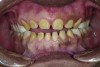

Figure 5. Preoperative 1:1 retracted frontal view.

Figure 5

The authors report on a 21-year-old patient who presented with severe discoloration and mild sensitivity of teeth (Figure 1). The teeth visible in his smile were very short, unsightly, and unbecoming for his age.

A thorough clinical examination and analysis were carried out to assess the esthetic and functional problems of the patient (Figure 2 through Figure 7). The medical history was non-contributory, except for mild leukoderma. Temporomandibular joint (TMJ) function was within normal range.

Mounted study casts were used to evaluate occlusion. The relevant findings were as follows2: Facial analysis revealed a canted maxillary occlusal plane and canted dental midline. Dentolabial analysis showed that the maxillary incisors were not adequately visible during repose; it also revealed a reverse smile line, as well as a wide smile showing 12 teeth. Results from the phonetic analysis were that “F” and “V” sounds revealed upper incisal shortening, “M” and “S” pronunciation disclosed a diminished vertical dimension of occlusion (VDO), and “E” sounds showed severe shortening of incisors. Dental analysis revealed thick biotype, asymmetry and inappropriate location of gingival levels and zenith, incorrect axial inclinations, a displeasing width-to-length ratio, and pitted surfaces on most teeth. Interproximal decay was evident on several posterior teeth, as revealed by radiographic analysis. Finally, occlusal examination indicated discrepancy between maximum intercuspation (MIP) and centric relation (CR) as well as a lack of anterior guidance/posterior disclusion.